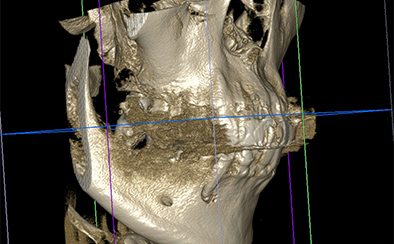

歯科用CTにより、歯や顎の3D画像を作成することができます。肉眼では見えない根管の構造をあらゆる方向から正確に映し出せるため、病変の大きさや原因を詳細に把握し、より精密な診断ができるようになります。

現在の歯の状態を正確に診断するために、歯科用CTなどの各種精密機器を用いて精密検査(デンタルドッグ)を行います。精密検査の結果をもとに診断を行い、どのように治療を進めていくべきか検討します。治療についてご説明した後、患者さんの同意を得てから治療を始めていきます。